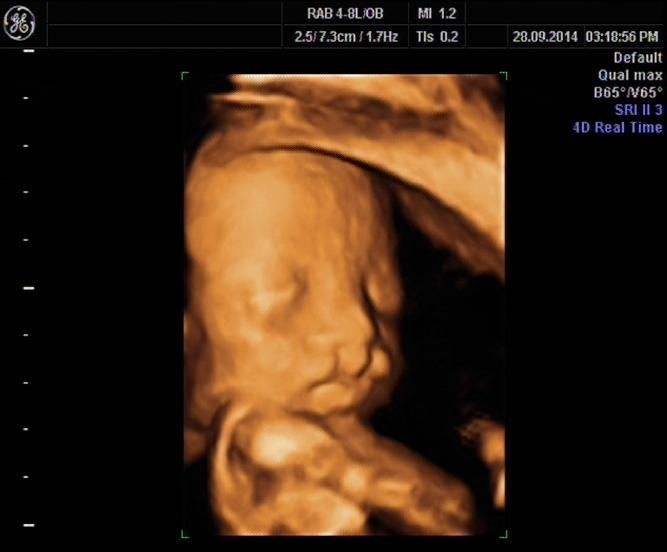

直到26周做彩超的时候,医生说胎儿唇部中心线扭曲可能是兔唇,全家人如遇五雷轰顶,无论如何也不能相信这个事实,后来又辗转跑到妇幼保健院再次做了四维彩超,再次确认孩子确实有兔唇的情况。小李顿时哭的稀里哗啦,自己平时非常注意又不抽烟也没有家族遗传,孩子怎么可能有兔唇呢。